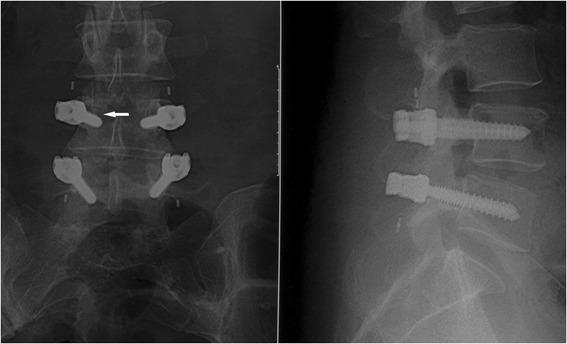

Polyetheretherketone (PEEK) rod system is a novel pedicle-based dynamic stabilization system. This study evaluated clinical and radiographic outcomes of non-fusion surgery by PEEK rod systems for treatment of degenerative lumbar diseases with a 2-year follow-up.

From February 2012 to October 2012, 38 patients who underwent non-fusion surgery using PEEK rod systems were included in the study. Data on Oswestry Disability Index (ODI) score and Japanese Orthopaedics Association (JOA) score were collected and radiographs were obtained to evaluate disc height index (DHI) and range of motion (ROM) at each interval.

Both JOA and ODI scores significantly improved postoperatively. DHI showed a slight increase immediately after the surgery but gradually dropped below preoperative levels. Mean ROM values changed from 8.8° preoperatively to 1.8° at the 2-year follow-up point. Screw loosening occurred in one case at the 2-year follow-up.

The preliminary results indicated a significant improvement in clinical outcomes and advantageous implant safety. The non-fusion procedure using PEEK rod systems might be a viable alternative for treatment of lumbar degenerative diseases. The distraction technique needs to be improved for better postoperative DHI.